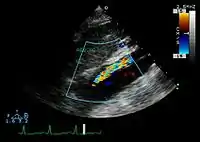

![]() |

![]() | |

An تخطيط صدى القلب displaying the true lumen and false lumen of an aortic dissection. In the image to the left, the intimal flap can be seen separating the two lumens. In the image to the right, color flow during ventricular انقباض القلب suggests that the upper lumen is the true lumen. | ||